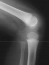

XRAY EVALUATION:

Radiographic examination of the left knee revealed no osseous abnormalities . A fullness of the soft tissues was evident over the fibular head. MRI examination of the left knee displayed a 2 cm. by 0.8 cm. lobulated mass in the region of the common peroneal nerve with no enhancement . On the T-2 weighted sequences there was abnormal increased signal of the tibialis anterior, extensor digitorum longus and peroneus longus muscle bellies suggesting atrophy . EMG/NCS were performed which clearly documented electrodiagnostic evidence of a severe peroneal neuropathy distal to the take-off of the nerve to the short head of the biceps.